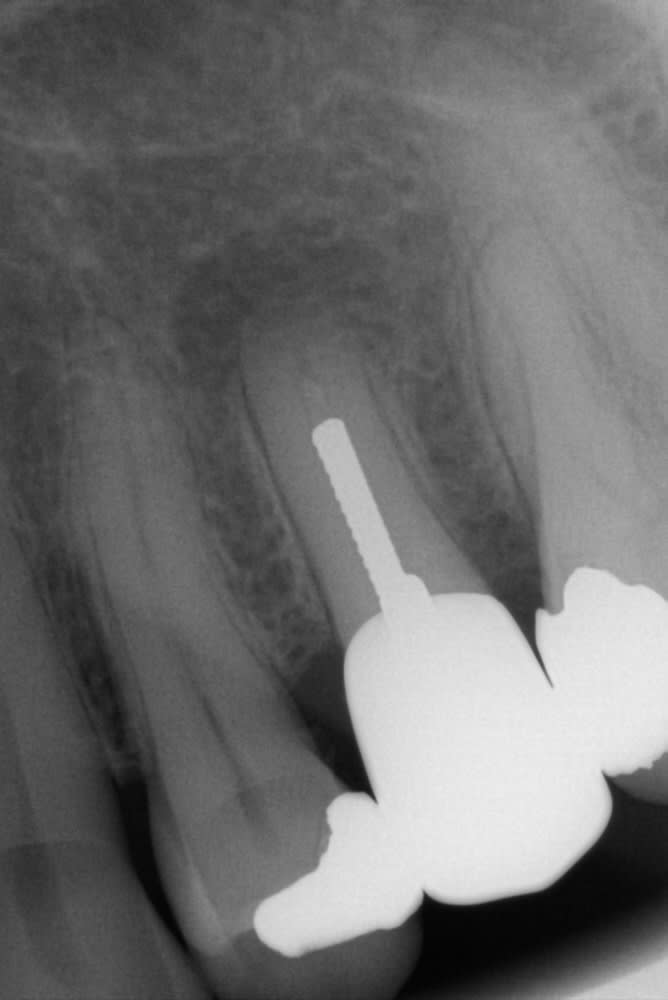

Ce patient avait une grosse infection sur la 25 et malgré plusieurs séance d hca cela ne cicatrisait pas. j, ai donc décidé avec lui de tenter une ERI.

voici la radio de contrôle du patient a 2 ans.